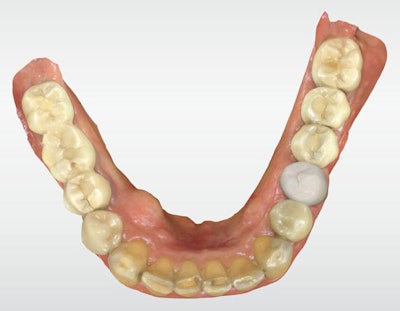

A 65-year-old healthy man presented for a hygiene visit and exam with a large, failing distal-occlusal amalgam on tooth #20, a mesial marginal ridge fracture, mesial recurrent decay, and buccal cuspal wear with cupping erosion (figure 1, below). An intraoral image illustrating the condition of the tooth was taken with Primescan (Dentsply Sirona) for patient education. The clinical image was shown to the patient and, upon being advised of the findings, he agreed to proceed with a CEREC (Dentsply Sirona) single-visit, full-contour crown restoration.

After the composite buildup and preparation were complete, the lower jaw, upper jaw, and buccal bite were recorded using the CEREC Primescan in the acquisition phase. The virtual models were created, and the crown was designed using the CEREC 5.1.1 software (figure 3, below).